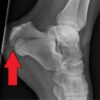

Calcaneal fractures account for 60% of tarsal fractures, and intra-articular fractures account for up to 75% of those. Displaced intra-articular calcaneal fractures are often accompanied by long-term sequelae, permanent disability and other...